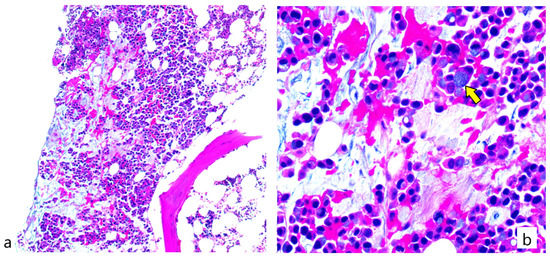

2. Case